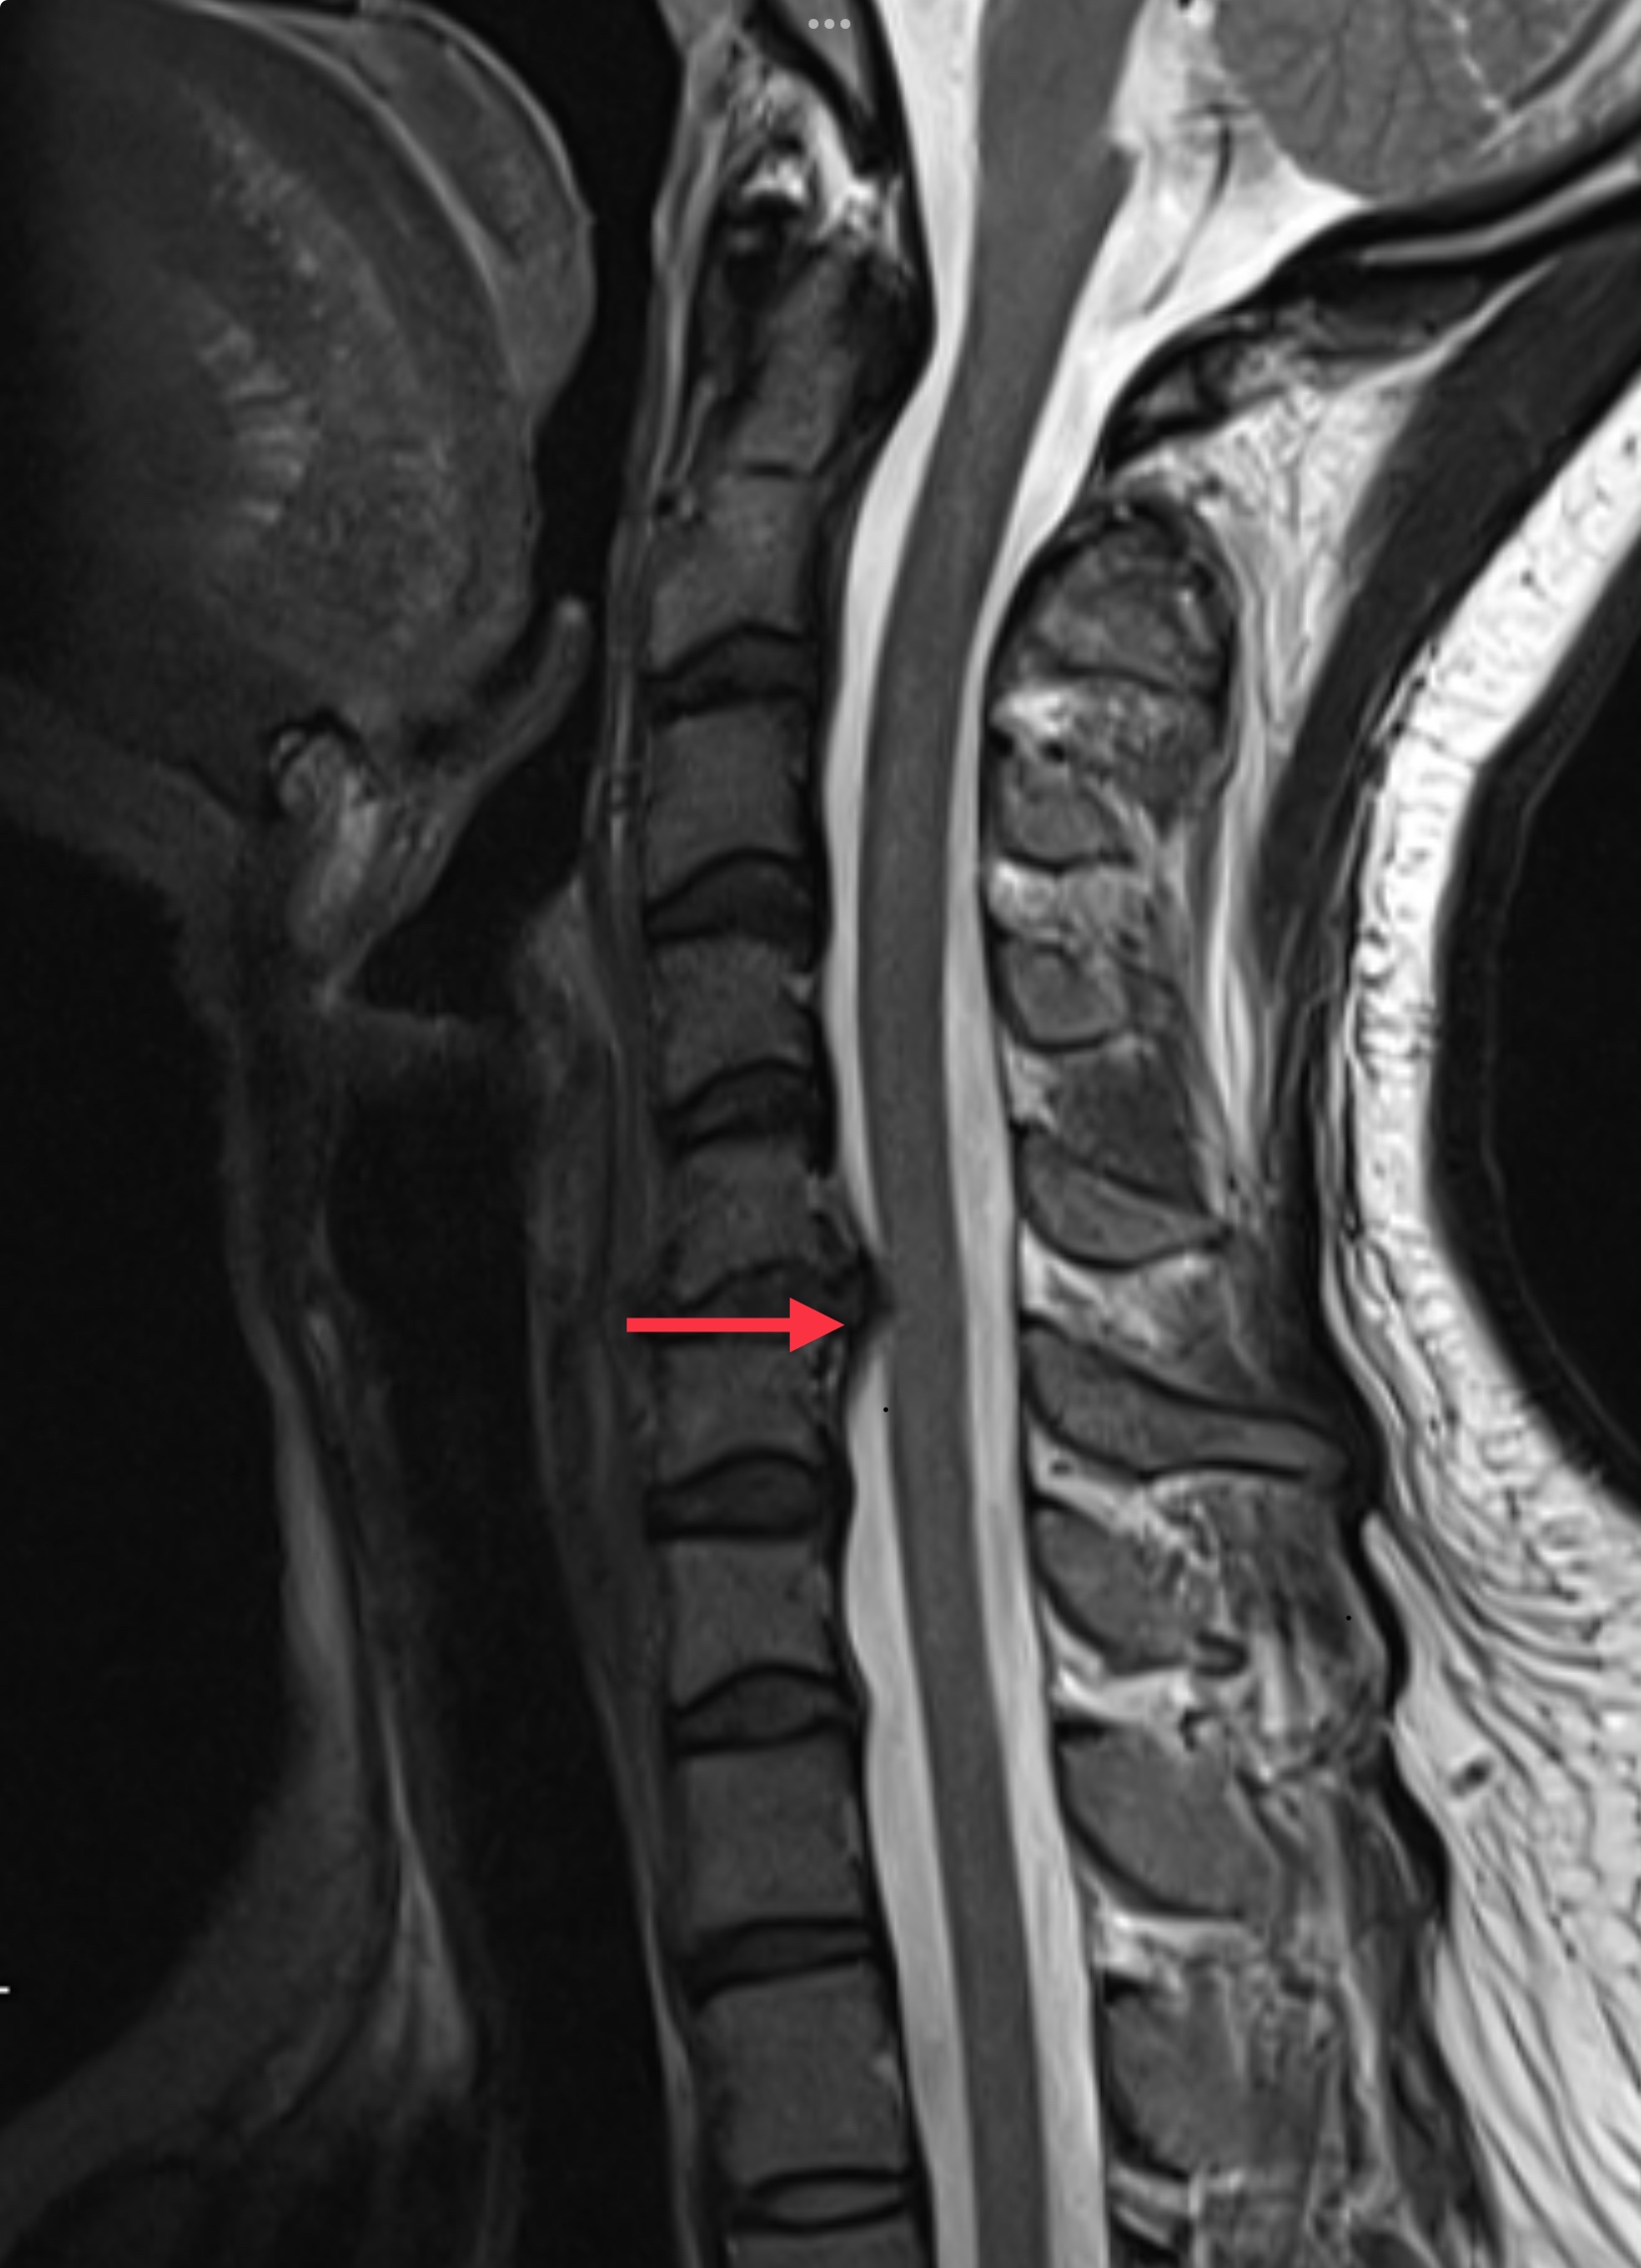

หมอนรองกระดูกคอทำหน้าที่เหมือน “โช้คอัพ” ที่ช่วยรองรับแรงกระแทกระหว่างกระดูกสันหลัง เมื่อหมอนรองกระดูกเสื่อมสภาพหรือเคลื่อนตัวออกจากตำแหน่งเดิม จะทำให้เกิดการกดทับเส้นประสาทที่อยู่ใกล้เคียง ส่งผลให้เกิดอาการปวด ชา หรืออ่อนแรงในบางกรณี

4. ภาวะที่ส่งผลต่อไขสันหลัง

• หากหมอนรองกระดูกเสื่อมจนกดทับไขสันหลัง (Myelopathy) คุณอาจมีอาการเดินไม่มั่นคง รู้สึกเสียสมดุล หรือมีปัญหาในการควบคุมการเคลื่อนไหว หากปล่อยไว้นานโดยไม่รักษา อาการนี้อาจทำให้เกิดความพิการถาวรได้